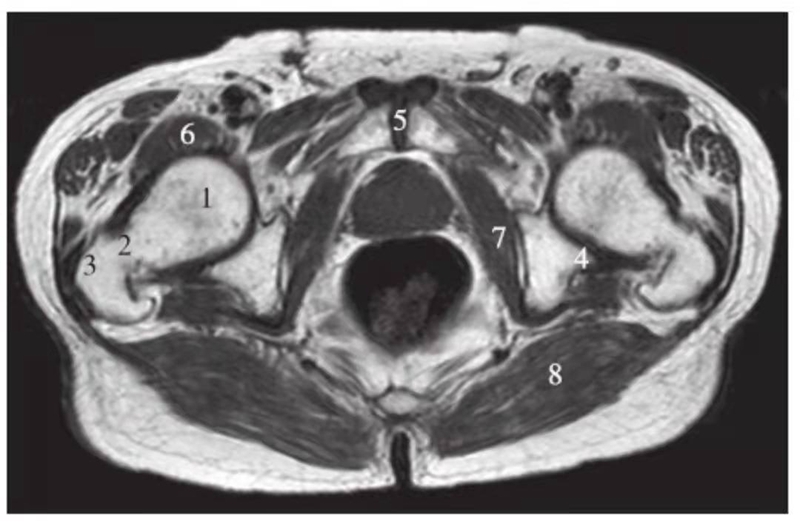

正常髋关节经股骨颈层面T1WI像

1.股骨头;2.股骨颈;3.转子间部;4.髋臼后唇;5.耻骨联合;6.髂腰肌;7.闭孔内肌;8.臀大肌